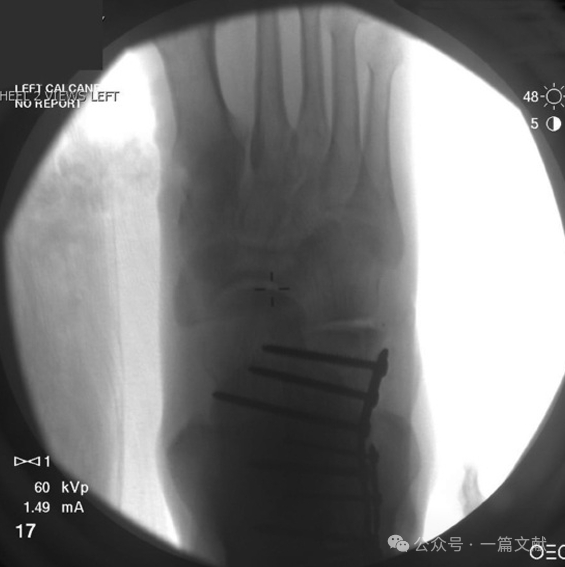

四,术中拍摄的各影像图如下:

3.3 足正位片:可观察次骨折线累及跟骨前份,并可评估跟骰关节面情况。如下图:

拍摄体位如下: